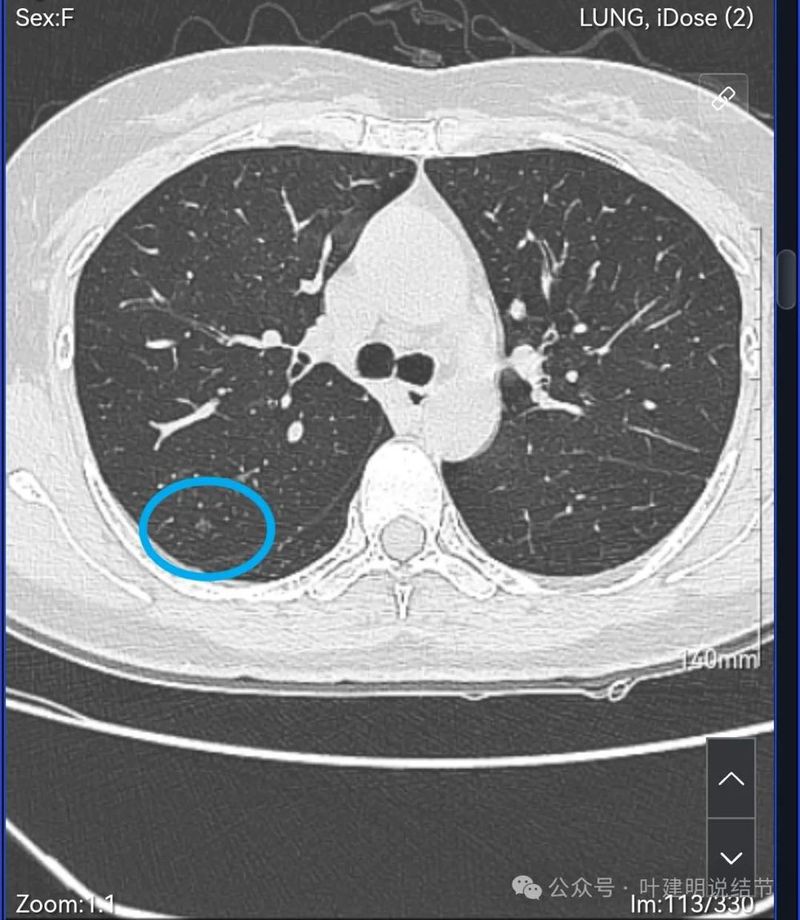

病灶1:右上叶后段磨玻璃结节,较小,轮廓较清,密度低,没有实性成分。

右肺多发磨玻璃结节,红色的是主病灶,密度不纯,贴着叶间裂,分叶明显,考虑至少微浸润性腺癌,也可能是浸润性腺癌贴壁为主型,不能继续随访,建议手术切除,可以单孔胸腔镜下局部楔形切除。黄色的也是磨玻璃,不典型增生或者肺泡上皮增生可能性大,蓝色的肺泡上皮增生可能性大。这两处风险还低,但如果主病灶需要处理,也可以考虑同期切除。意见供参考!